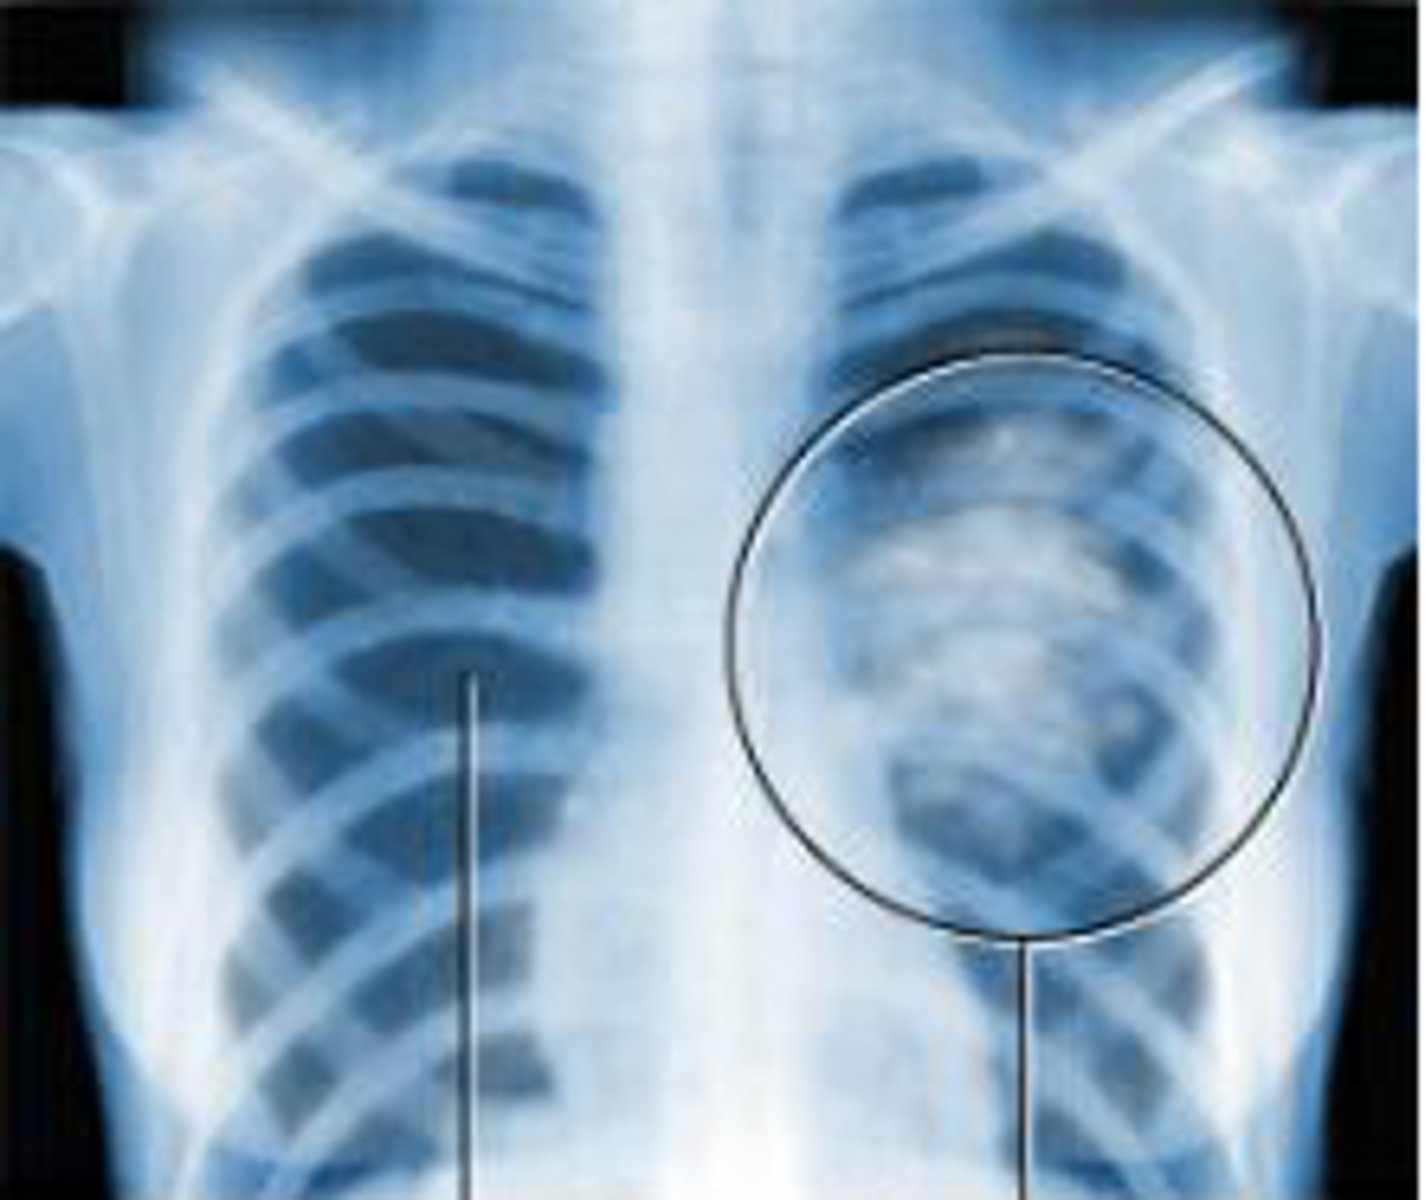

cancer

tumour